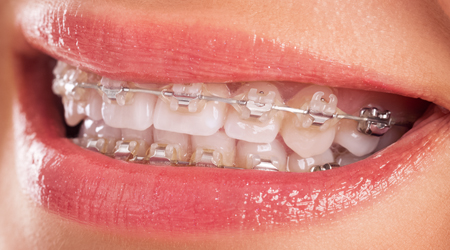

Orthodontics & Clear Braces

Braces Treatment INR US

Braces (Metal) 30000 450

Braces (Metal)- Smartclip 3M 55000 850

Braces (Ceramic)- Clarity TM SL 75000 1150

Braces (Ceramic/Metal)- DAMON 65000 1000

Braces (Lingual) 75000-150000 1000-2300

Clear Aligners (K-LINE,Germany) 80000-250000 1200-3800

Clear Aligners (Invisalign) 100000-450000 1535-7000